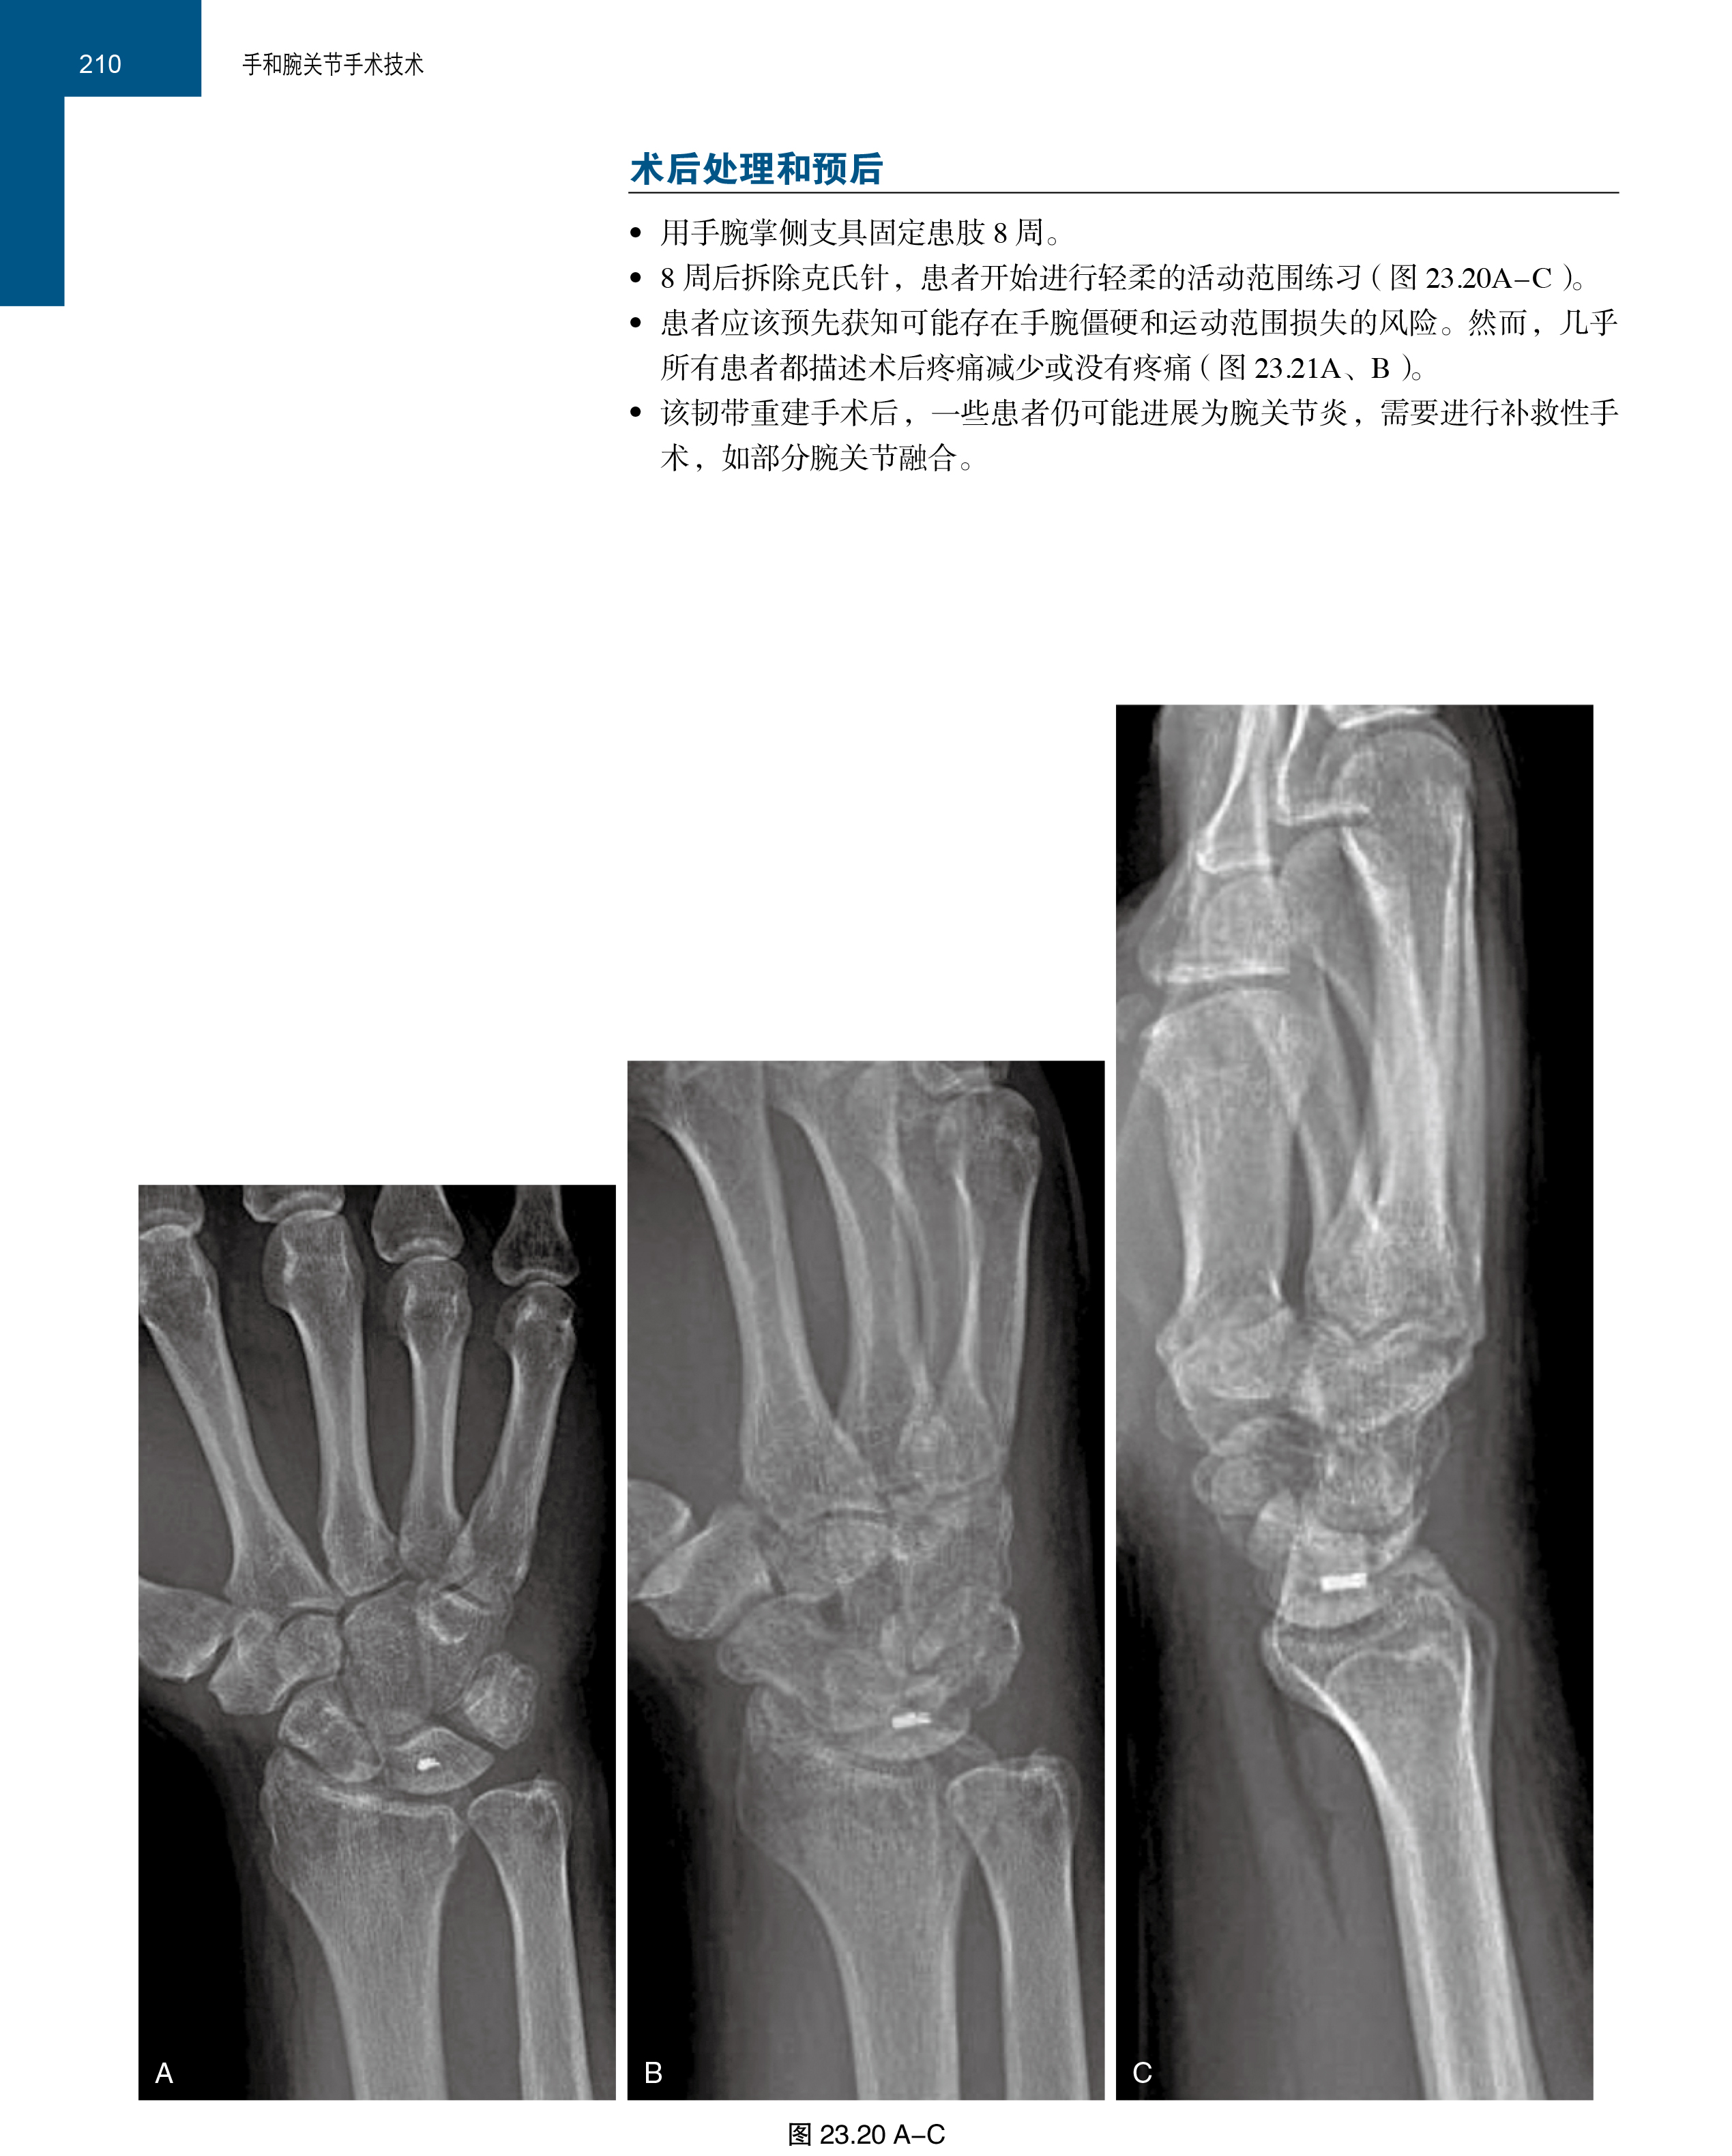

本书内容丰富,为您提供了前沿、实用的手和腕关节手术技术资料,并教您如何完成各个手术步骤。在本书的各章节中,对于当前手和腕手术的热点问题,如桡骨远端骨折与畸形愈合、腕关节镜、神经和肌腱移植、皮瓣与显微外科等都进行了清晰、准确且详尽的描述,能使每一位骨科医生受益匪浅,更是各级医师必备的权威教科书。